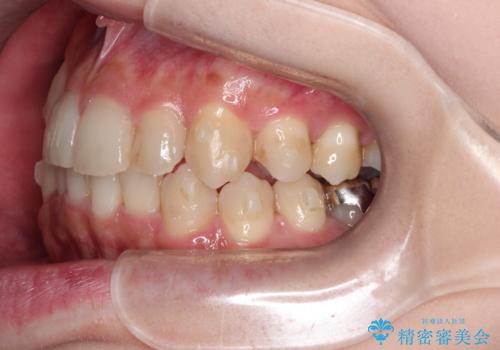

- 八重歯を治したいとのことで来院されました。

右上の犬歯が外側に飛び出して、二番目の歯が内側に入っている状態でした。

上の奥歯を後方に移動させてスペースを確保して、前歯のガタガタを改善する計画としました。